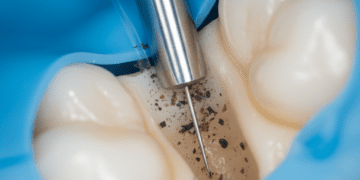

Um dos aspectos mais importantes é o nível de detalhe radiográfico da imagem. Altos níveis de detalhe permitem que professionals identifiquem pequenas fraturas, cáries incipientes e outras anomalias que poderiam passar despercebidas em imagens de menor qualidade. Para isso, é crucial que a tecnologia utilizada seja de ponta e que a técnica de exposição seja ajustada corretamente.